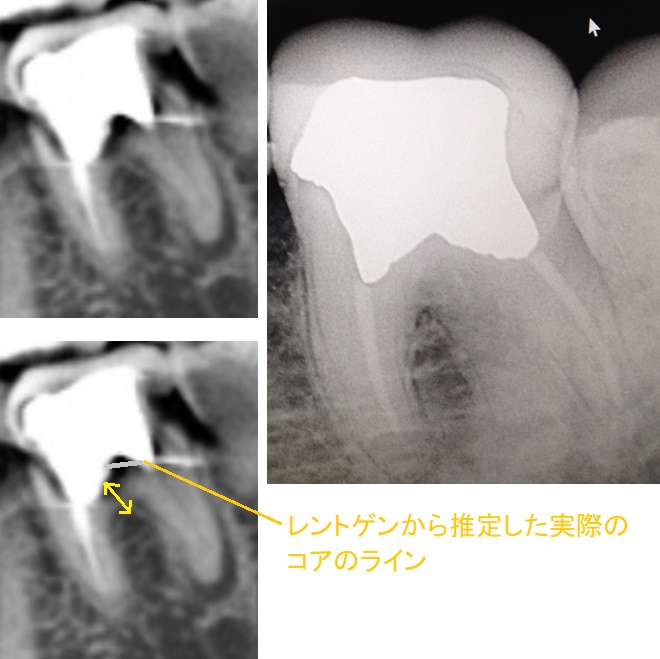

2012年にRCTを終え歯冠修復をした左下6番に大きなメタルコアが入っています。元々は、メタルクラウンだったのですが、2018年にクラウンのみハイブリッドレジンCAD/CAM冠に変更しています。

数軒歯科医院を回りましたが、メタルコアの底辺と根分岐部が近いため、外すのが怖くてようせんという医師が多かったです。

1)CTとレントゲン画像のみの判断になりますが、実際には奥行きもありますし、結局、こうやって画面で見ると2次元で見ることになるのでコアの底辺と根分岐部が前後にどれだけズレているかもわかりません。しかし、どっちにしてもクラウンが被っている歯を見たところで何もわからないため、CTとレントゲン画像で判断するしかないため、診察をしての判断もあまり変わらないと思います。この状態のメタルコアを破折させずに外せそうでしょうか?私が見る限り、そーんなにギリギリでもなさそうですけどね。(写真黄色の矢印部分)

2)メタルコアを無事外せたとして、再RCTでのファイルを使用する時の振動による根分岐部の破折も可能性としてあるでしょうか?

根尖病変があるため、どうにかして無事メタルコアを外して再RCTを済ませたいのです。

@ 普通に外す症例ですね、当院では。

まあ心配なら遠心側のコアだけ外せば根管治療はできそうです。

遠心根の根尖部には明らかな黒い影があるので治療対象にしてもおかしくないですね。

近心根の根尖部は正常にみえますが側枝がありそうで少し歯根の手前側に黒い影らしきところがあるかもしれないと思います。

下顎第一大臼歯には3根4根管というパターンが結構あります。この歯は4根管性で1根管完全な見落としがあると思います。